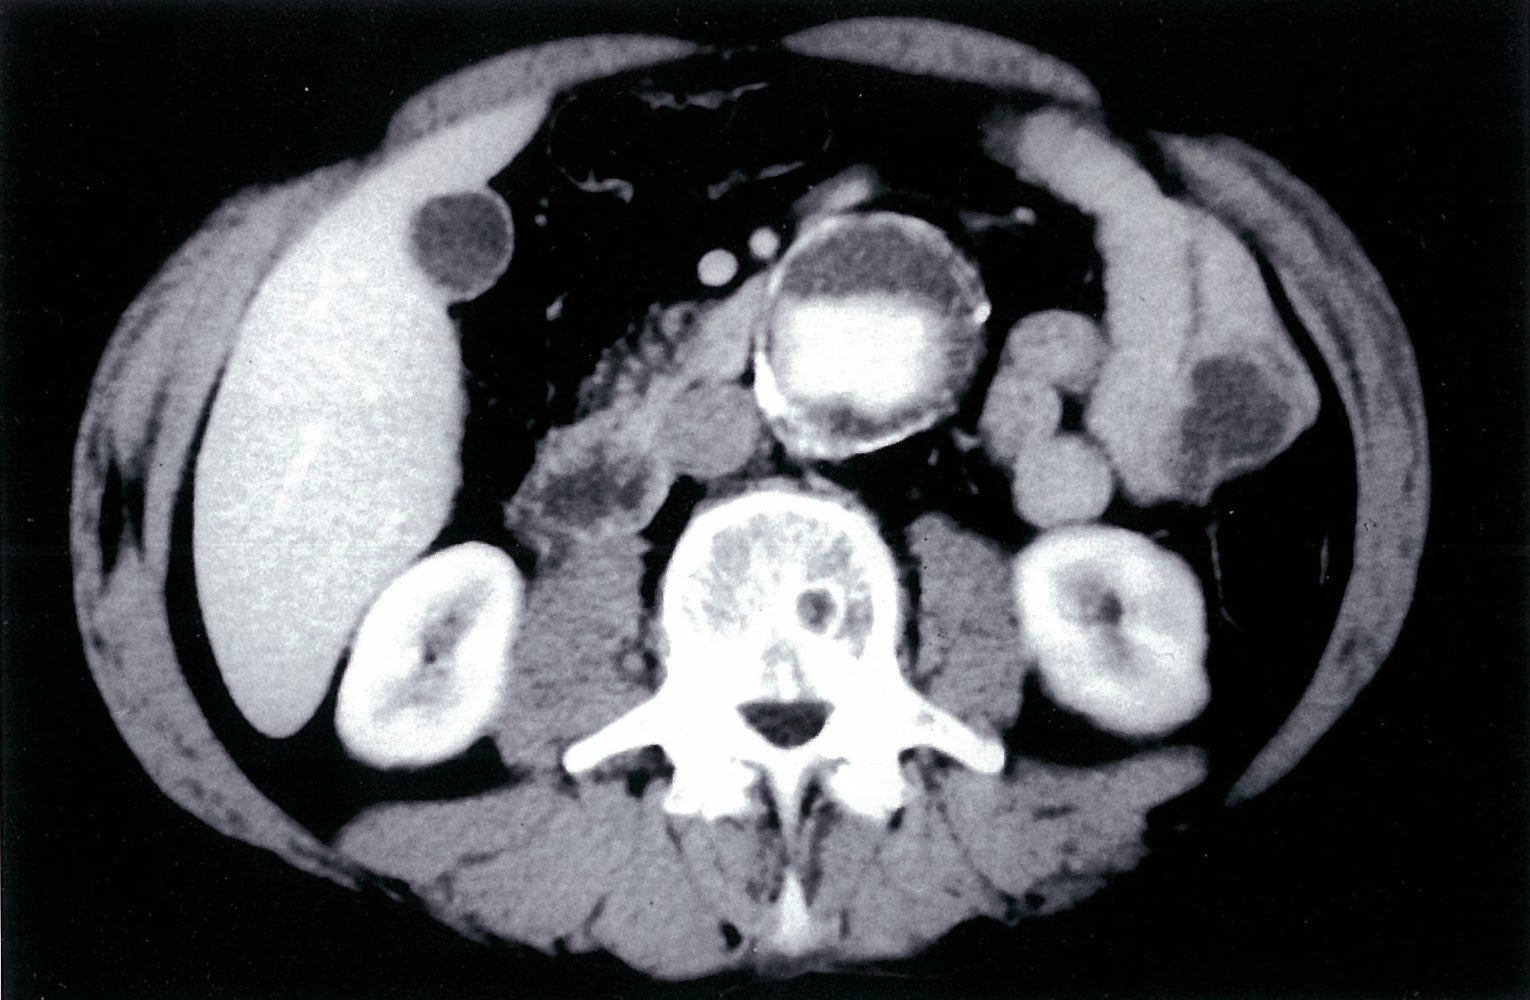

CT angiography abdomen and pelvis

See āRuptured AAAā for CT findings of acute aneurysmal rupture.

-

Indications

- Imaging modality of choice in symptomatic patients and for preintervention planning

- To help confirm the diagnosis when ultrasound is not possible in asymptomatic patients

- More detailed evaluation of the location, size, and extent of the aneurysm, involvement of branch vessels, and presence of thrombus or rupture

Supportive findings

- Dilatation of the aorta ā„ 3 cm and, possibly, branch vessels [1]

- Reduced distribution of vasa vasorum may be seen. [10]

- Thrombus may also be present (hypodense, nonenhancing).

![]()